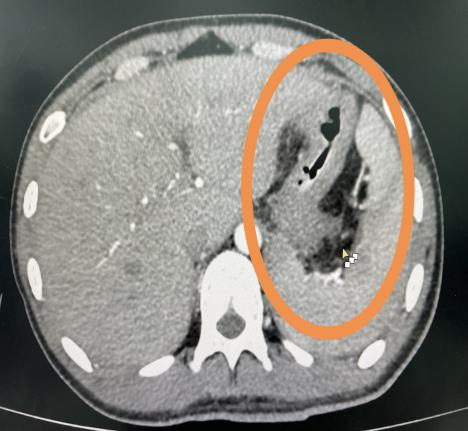

饮水前                                   饮水后